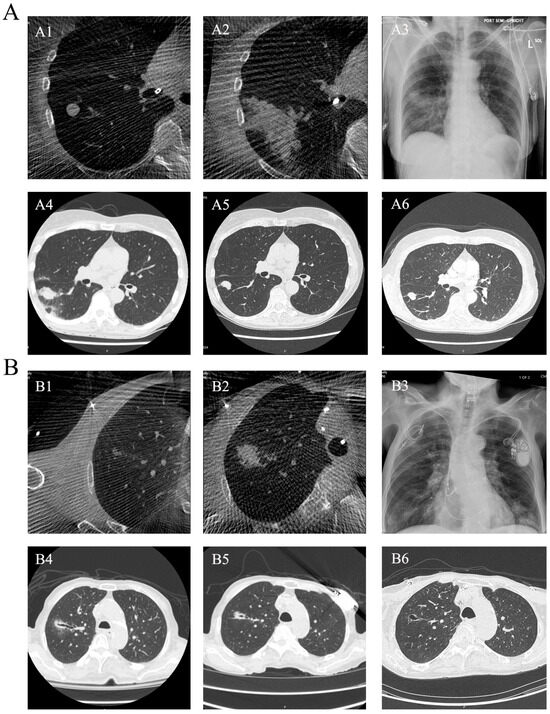

Shape-Sensing Robotic-Assisted Bronchoscopic Microwave Ablation for Primary and Metastatic Pulmonary Nodules: Retrospective Case Series

Background: Bronchoscopic thermal ablation has emerged as a minimally invasive therapeutic option for managing pulmonary nodules in patients unsuitable for surgery or radiotherapy. Robotic-assisted bronchoscopy (RAB) offers enhanced stability and precise navigation, potentially improving the safety and accuracy of bronchoscopic ablation. However, clinical data on RAB-guided microwave ablation (MWA) remains limited. Therefore, further evidence is needed to evaluate its feasibility, safety, and early therapeutic performance. Methods: We conducted a single-center retrospective feasibility study of shape-sensing RAB-guided MWA (ssRAB-MWA) for pulmonary nodules between October 2024 and September 2025. Eligible lesions (≤3.0 cm) included both primary lung cancers and metastatic nodules. All procedures were performed under general anesthesia using the ssRAB system integrated with cone-beam CT for intra-procedural confirmation. Technical success, safety outcomes, and short-term efficacy were assessed. Results: Nine patients (with 11 lesions: 3 primary, 8 metastatic) underwent ssRAB-MWA with 100% technical success. The median ablation time per nodule was 10 min (range, 1–26). One patient developed post-ablation pneumonia requiring hospitalization; no pneumothorax, major bleeding, or airway injury occurred. All lesions exhibited a transient increase in size immediately following MWA, followed by gradual reduction or stabilization over time. PET-CT evaluation demonstrated metabolic remission in primary lesions, with one patient achieving pathologic complete response after surgery. Conclusions: ssRAB-MWA appears to be a feasible and safe navigation-guided technique for small pulmonary lesions, offering encouraging early local control in both primary and metastatic lung cancers. This platform may expand the therapeutic spectrum of interventional pulmonology, bridging diagnosis and local therapy. Larger multicenter studies are warranted to validate long-term outcomes. Full article

Figure 1